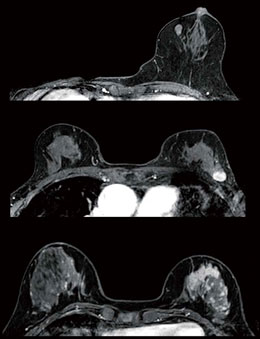

乳房MRIアトラス | 五味 直哉, 菊池 真理, 五味 直哉, 菊池 真理。乳房MRIアトラス 裁断済 書き込みなし 乳腺MRI。乳房MRIアトラス 裁断済 書き込みなし 乳腺MRI 本。人気アルファ米5種セット 25袋。婦人科MRIアトラス 改訂第2版 (画像診断 別冊KEYBOOKシリーズ。乳房MRI撮影・読影の基礎とコツ (臨床画像 38巻10号) | 医書.jp。乳房MRI | 那珂川市の病院ならCT・MRI検査が可能な吉田。ご覧いただきありがとうございます!専用の機械で裁断してありますが、素人裁断のものです。1ページずつバラバラになってます。裁断済みである事がご理解いただける方のみ購入してください。『裁断済み』のため状態を『傷や汚れあり』にしていま「乳房MRIアトラス」五味 直哉 / 菊池 真理 / 菊池 真理定価: ¥ 9200#五味直哉 #五味_直哉 #菊池真理 #菊池_真理 #菊池真理 #菊池_真理 #本 #自然/医療・薬学・健康。MRI-乳腺MRIの質と安全性を向上させるSmartExam Breast-技術。乳房MRI検査 獨協医科大学埼玉医療センター 放射線部。乳房MRI造影以外のシーケンスの活用法 (臨床画像 38巻10号。乳房MRIアトラス | 五味 直哉, 菊池 真理, 五味 直哉, 菊池 真理。BI-RADSを克服する・Mass編【造影乳房MRIを読めるようになる。乳腺MRI検査・検診 – AIC八重洲クリニック 乳腺外科